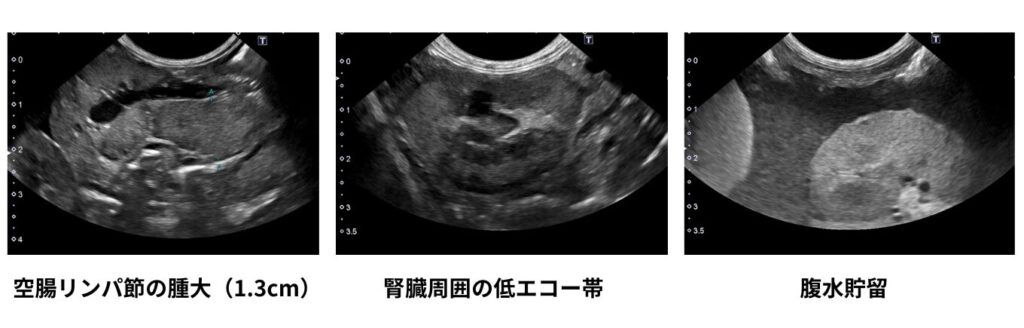

一方、超音波検査ではFIPを疑う特徴的な所見を捉えられることがあります。

主に確認すべきポイントは以下の通りです。

・腹水、胸水、心嚢水の有無

・腎臓周囲における混合エコー帯の存在

・リンパ節腫大の有無

・腸管筋層の偏在性肥厚や腫大の有無

これらはいずれもFIPで比較的よく認められる所見ですが、画像検査のみで確定診断に至ることは困難です。鑑別診断のためには、生検による細胞診、PCR検査、組織学的検査などが必要となります。特に臨床現場では、リンパ腫との鑑別が重要なポイントとなります。